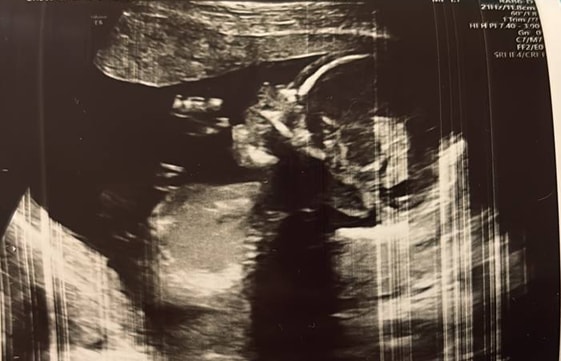

Вера, Изображение

Вера, да, подобные я видела, когда "в воздухе" кружочки ступней и ладошек. Видимо, аппарат при таком ракурсе не отображает ног и рук. У вас и ножку видно, это же ножка, не пуповина?

26.03.2025

Одуванчик, да, ножка) это прям удачный снимок, на мой взгляд) в пошлую беременность дочкой, там только животик и голова на память 😁